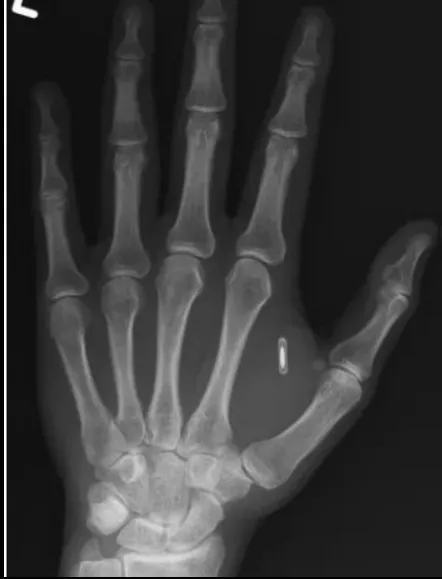

Чип у руці Цзи Тен Ваня. Фото: Facebook-сторінка Цзи Тен Ваня